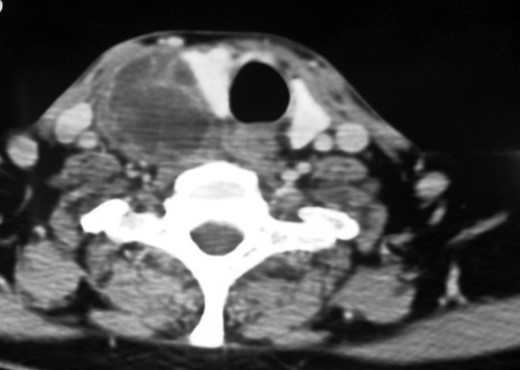

Computed tomography (CT) scan of the neck (with contrast) indicated a heterogeneously enhancing lesion with multiple cystic spaces along the postero-lateral aspect of the right lobe. The lesion was seen to push the adjacent lobe anteriorly to the left (Fig. 2). The lesion was also displacing the right common carotid and the internal jugular vein laterally; however, a well-defined fat plane was seen between the lesion and the carotid sheath. No such plane was seen between the lesion and the adjacent thyroid lobe (Fig. 3).

Contrast enhanced CT neck (axial section). Heterogeneously enhancing lesion with multiple cystic areas within abutting the postero-lateral aspect of the right lobe of thyroid, pushing it anteriorly and medially.